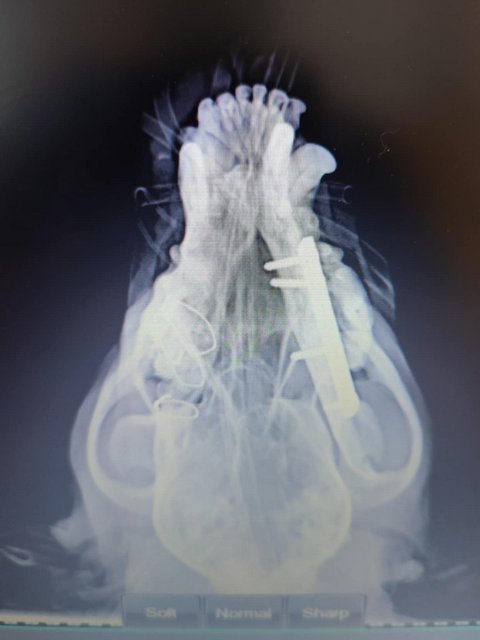

Röntgenbilder zeigten das Ausmaß der Zerstörung des Unterkiefers und den Bruch eines Beines.

Dieser Hund muss grausame Schmerzen haben, Zähne sind aus der Verankerung gerissen und sein Gesichtsschädel ist nicht mehr symmetrisch. Ein großes Stück des Unterkiefers ist komplett abgebrochen.

Camush Kopf ist wieder symmetrisch, der Kiefer wird jetzt mit Platte und Verdrahtung zusammengehalten und ein paar Zähne fehlen jetzt.